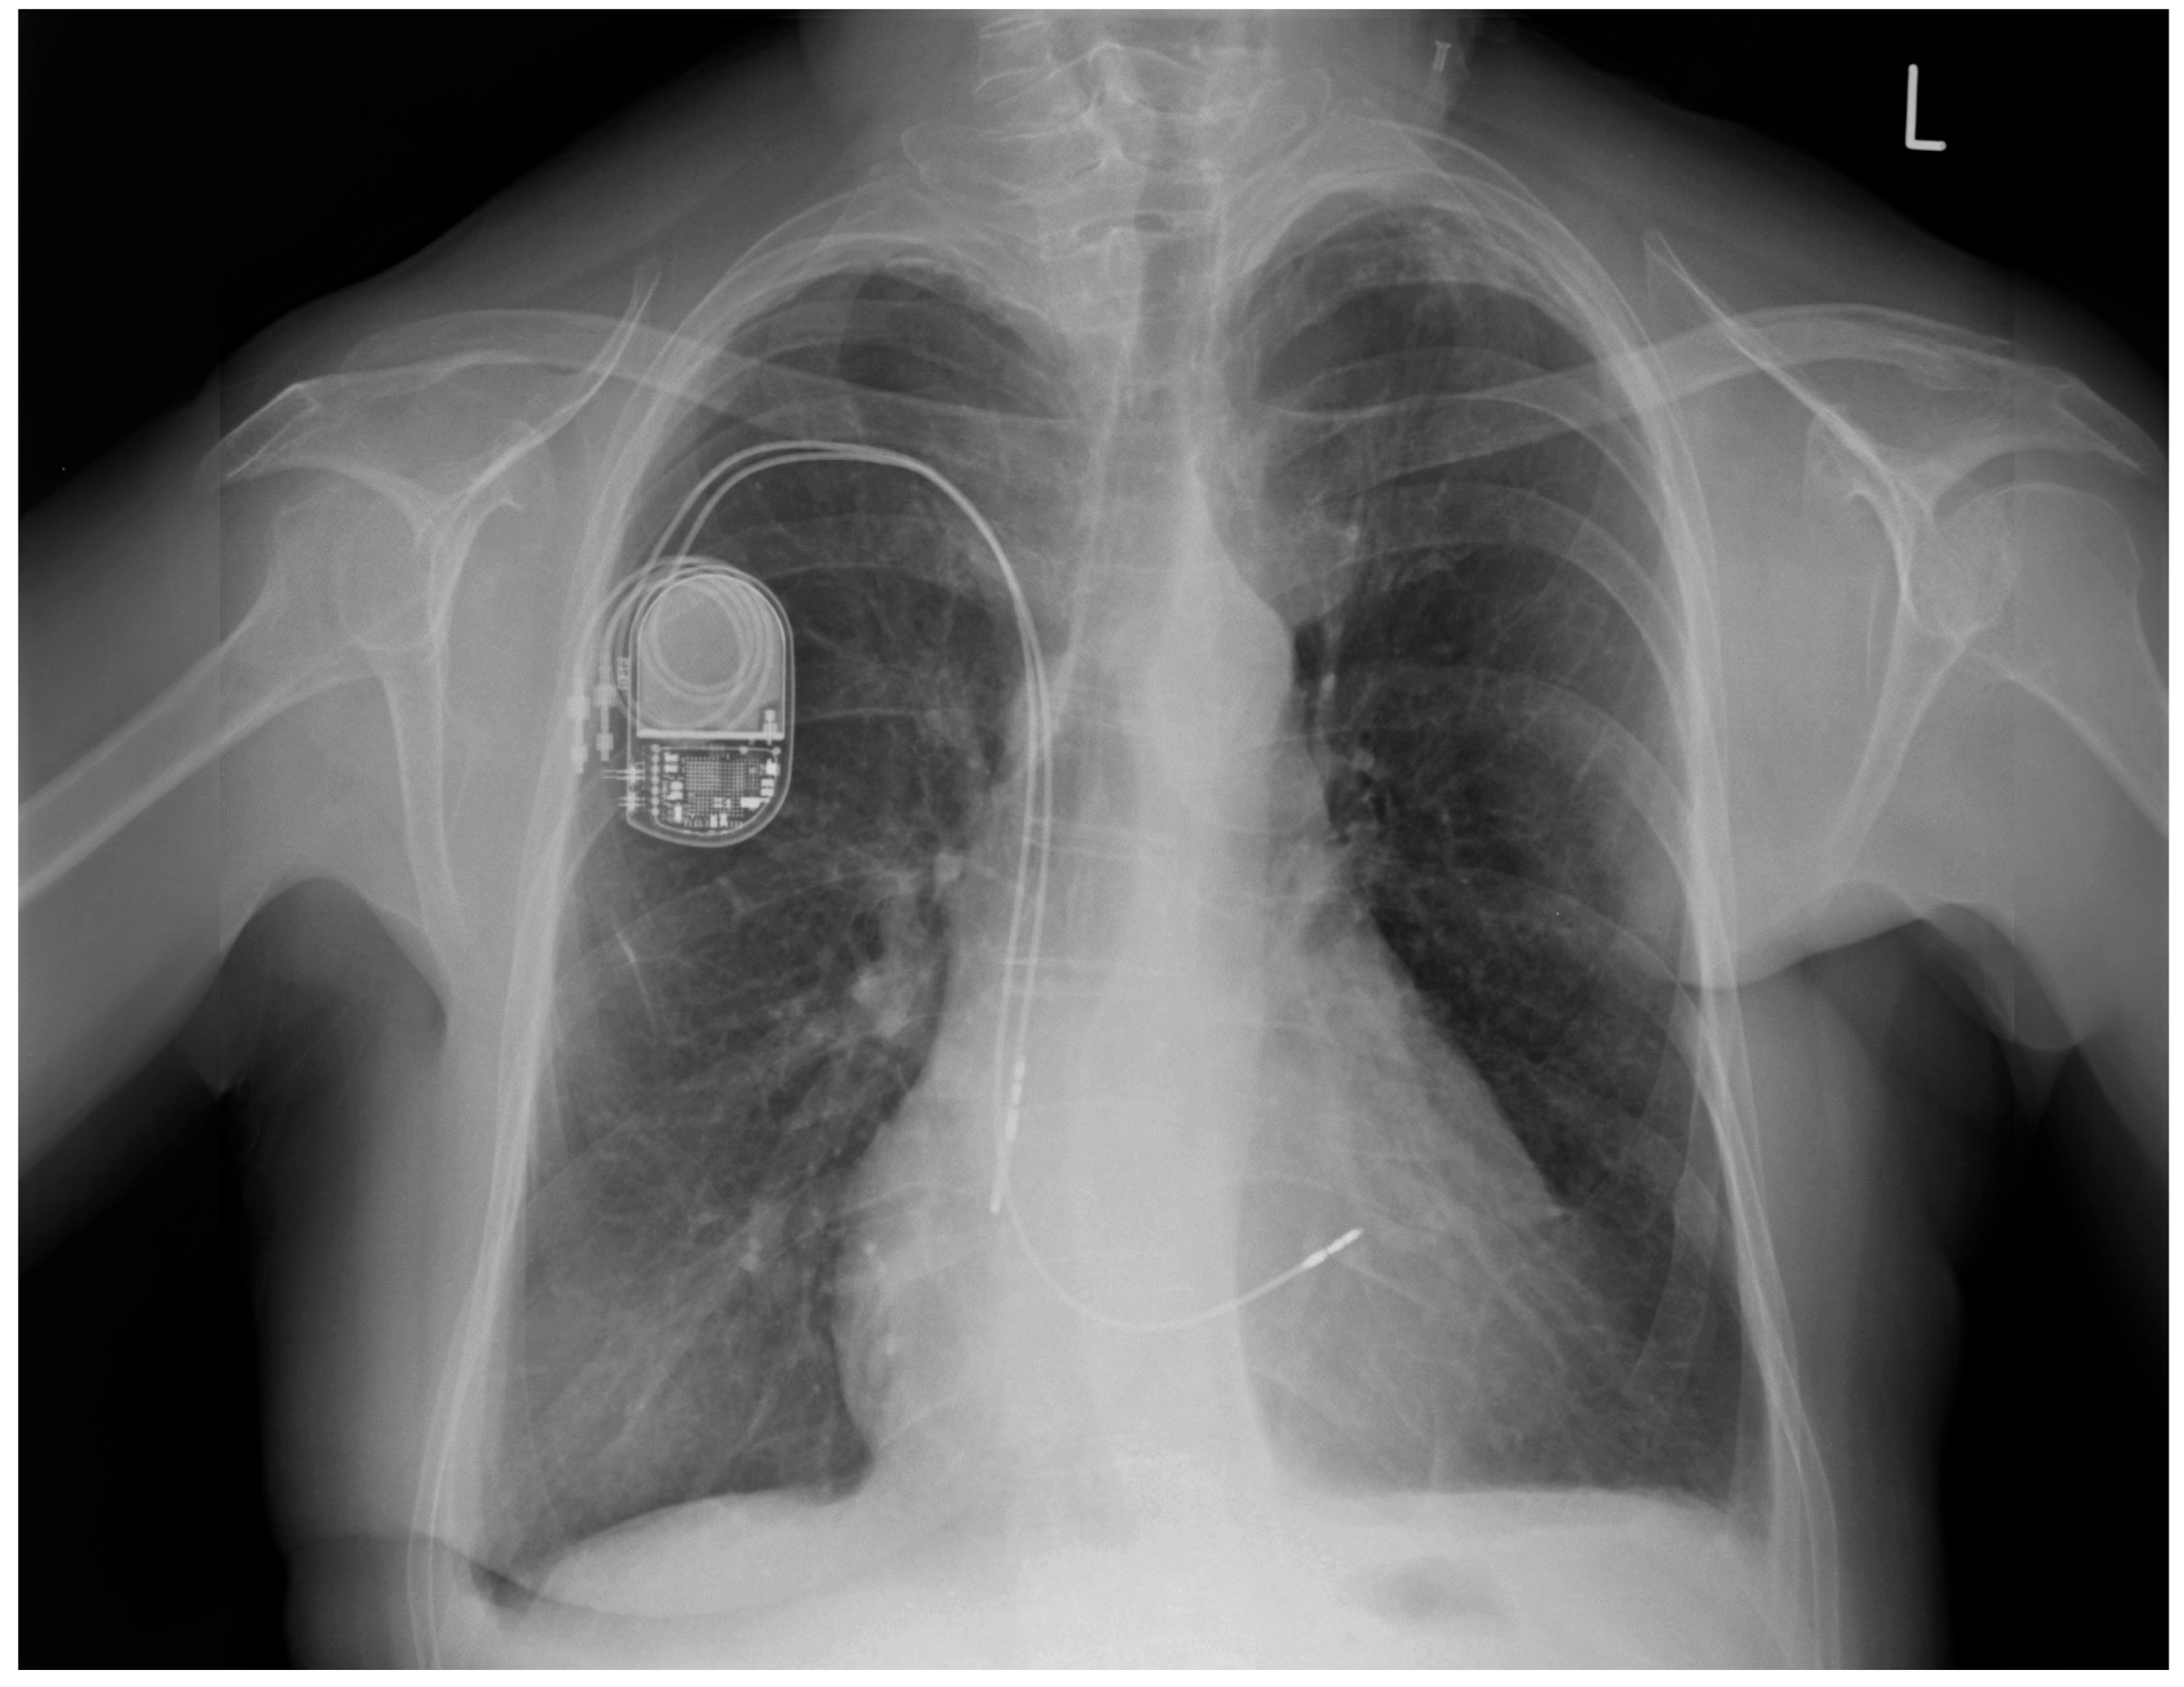

Six years earlier, the patient had a dual-chamber pacemaker implanted in the left subclavian area due to sick sinus syndrome (SSS). The patient underwent a mastectomy two years ago due to breast cancer. Post-mastectomy, she was qualified for thorax radiotherapy. As the pacemaker generator occupied the radiotherapy field, it was removed two years ago without removing the two remaining leads. A new pacemaker system was implanted into the right subclavian area (Figure 1).

Figure 1. Chest X-ray: abandoned ventricular and atrial electrodes (arrows).